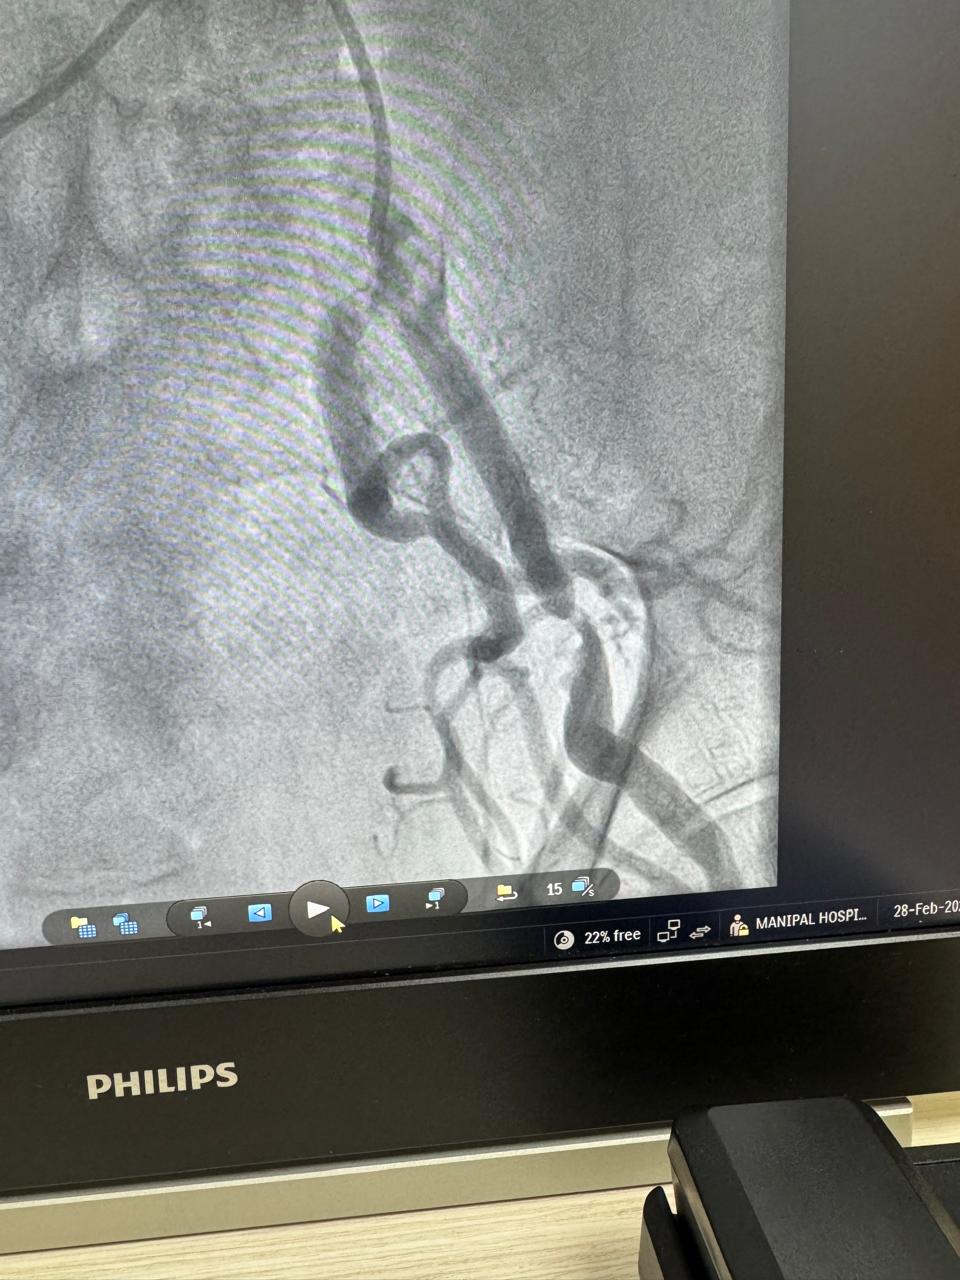

Angioembolization of traumatic right internal iliac artery ( posterior branch)injuries